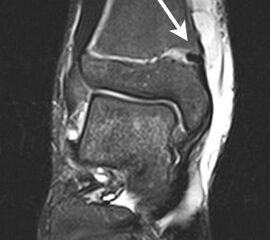

Os trigonum

Das Os trigonum lässt sich als isolierter Knochen dorsal des Talus seitlichen Röntgenbild darstellen. Normalerweise hat das Os trigonum keine klinische Relevanz. Bei entsprechenden Beschwerden und einer Aktivierung im MRT kann der Knochen arthroskopisch entfernt werden. Gehäuft beobachten wir eine mechanische Problematik durch das Os trigonum bei jugendlichen Fußballspielern und Tänzerinnen.